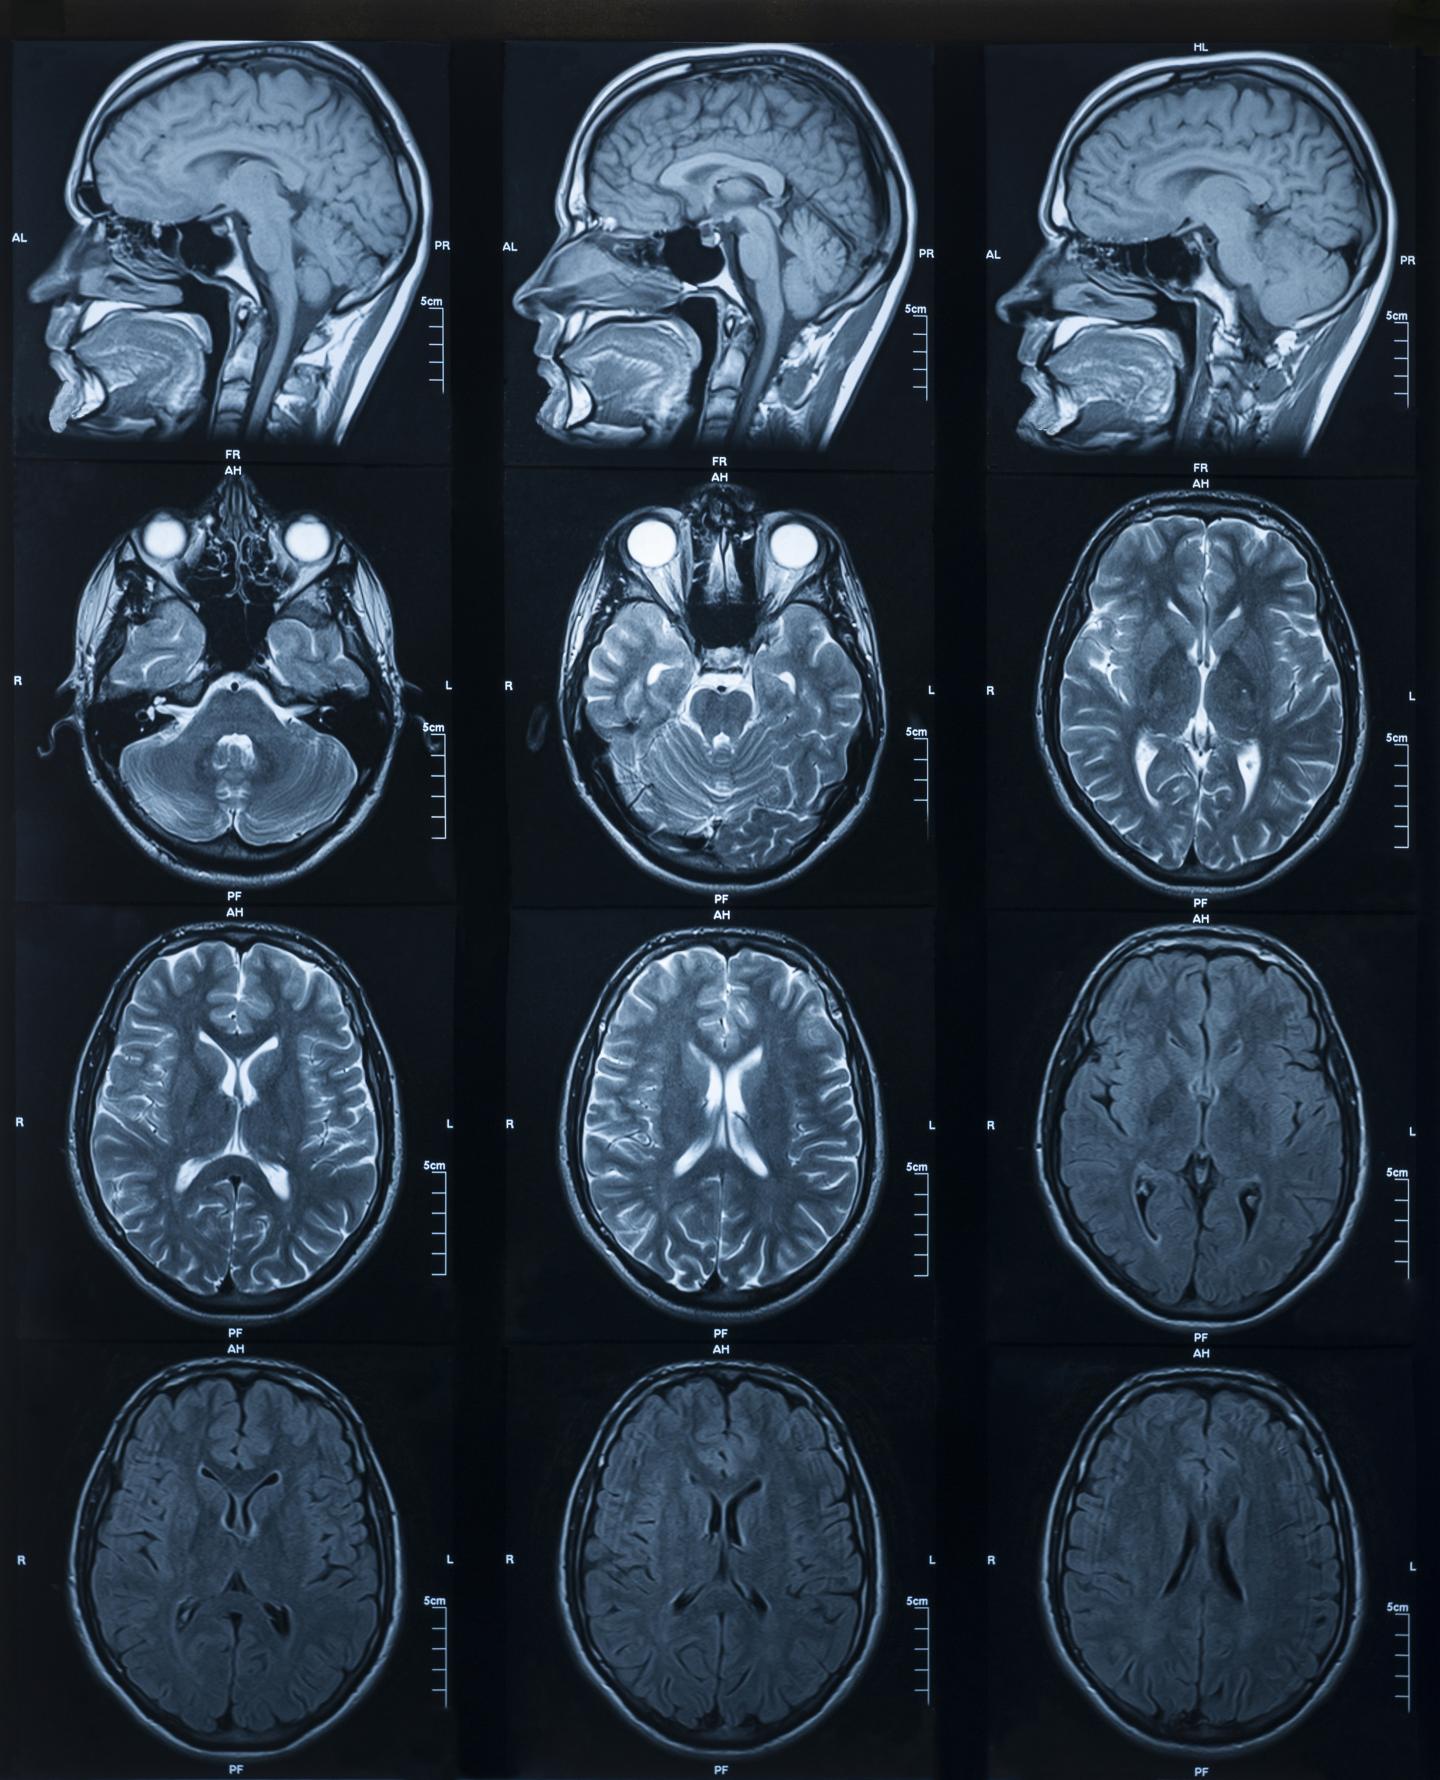

Mri Of Normal Brain Photograph by Science Source Why Mri Of The Brain Mri is used to analyze the anatomy of the brain and to identify some pathological conditions such as cerebrovascular incidents, demyelinating and neurodegenerative diseases. Magnetic resonance imaging (mri) of the head is a painless, noninvasive test that produces detailed images of your brain and brain stem. It produces images of blood flow to certain areas of the brain. An mri. Why Mri Of The Brain.

Why Mri Of The Brain . Magnetic resonance imaging (mri) of the head is a painless, noninvasive test that produces detailed images of your brain and brain stem. These include headache, seizures, sleep. An mri of the brain can be used to evaluate many symptoms which may be caused by abnormalities in the central nervous system. Mri may be used to examine the brain and/or spinal cord for injuries or the presence of structural abnormalities or certain other conditions, such as: Functional mri can be used to examine the. An mri machine creates the images. A special type of mri is the functional mri of the brain, also known as fmri. What are the reasons for an mri of the brain or spine? A neurologist would order an mri (magnetic resonance imaging) of your brain if they suspect something is wrong, if they are diagnosing an issue, or if they want to. It produces images of blood flow to certain areas of the brain. Mri is used to analyze the anatomy of the brain and to identify some pathological conditions such as cerebrovascular incidents, demyelinating and neurodegenerative diseases.